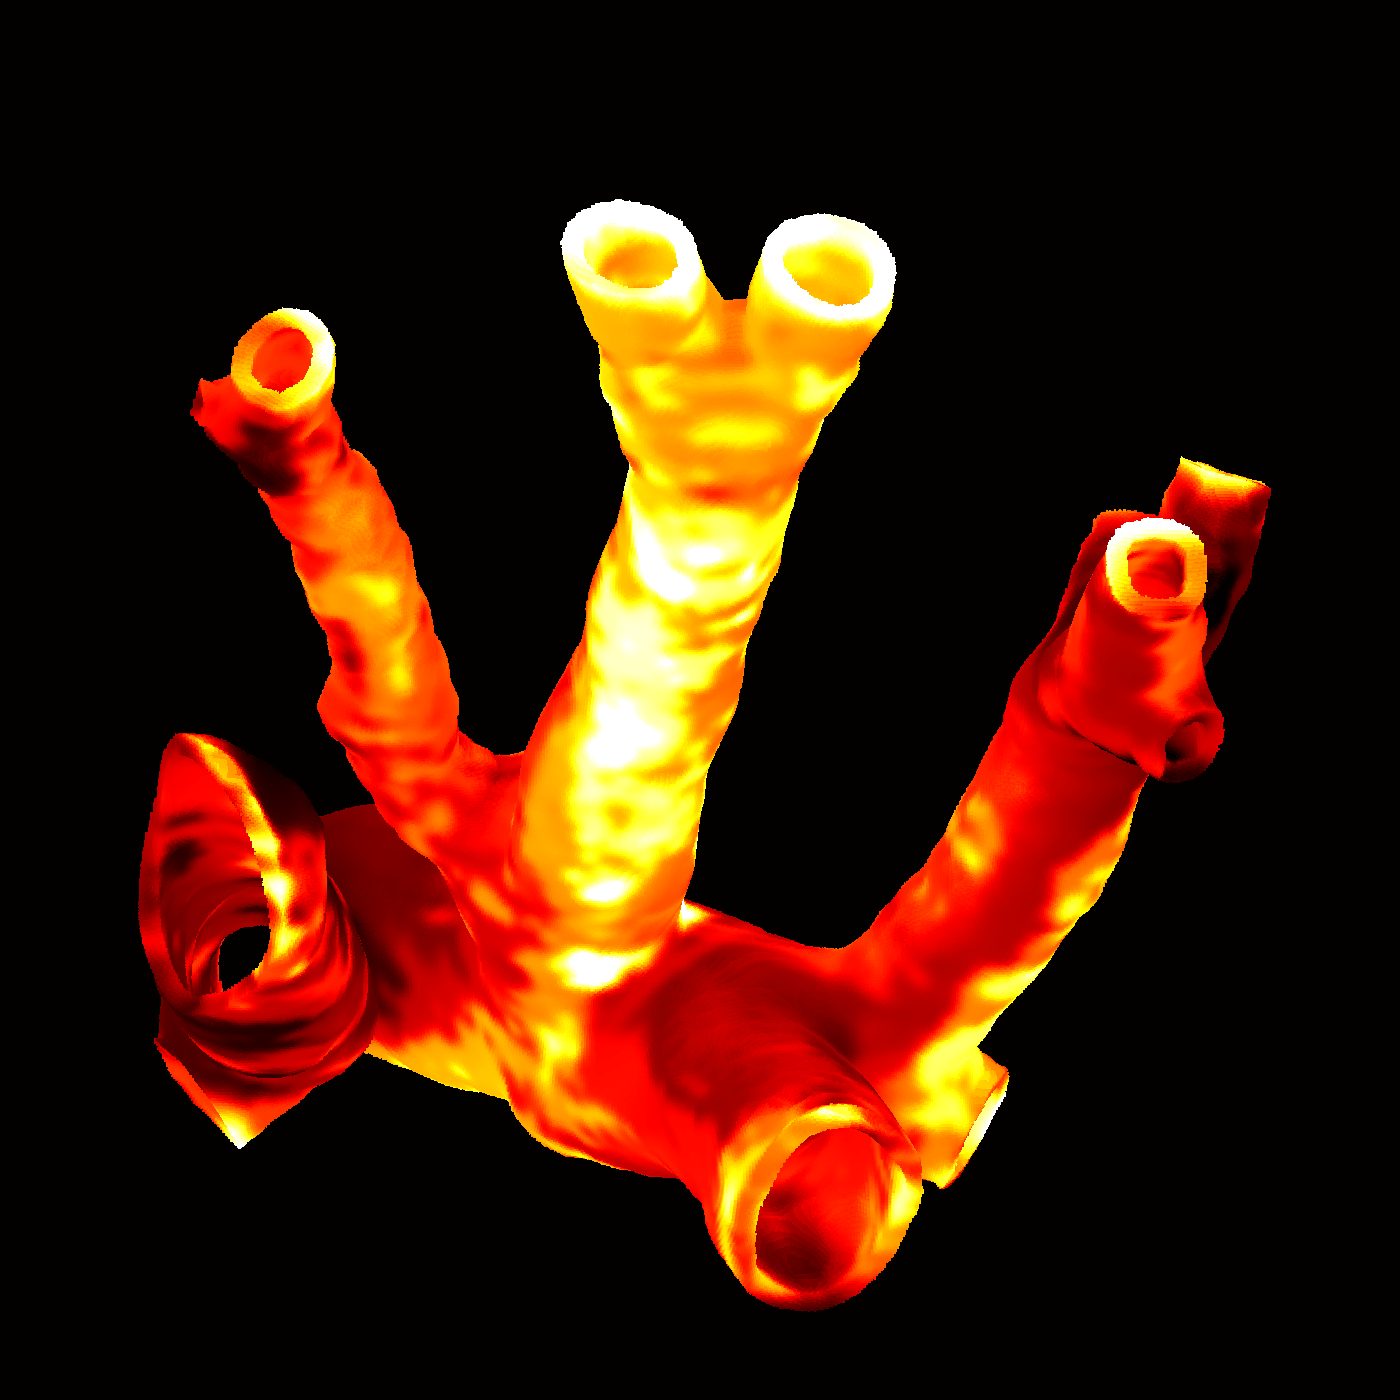

Bernal P., Bouwmeester M., Madrid-Wolff J., Falandt M., Florczak S., Rodriguez N., Li Y., Größbacher G., Samsom R., Wolferen M., Laan L., Delrot P., Loterie D., Malda J., Moser C., Spee B., Levato R., Volumetric bioprinting of organoids and optically tuned hydrogels to build liver-like metabolic biofactories, Advanced Materials, 2110054 (2022). |

Sgarminato V., Madrid-Wolff J., Boniface A., Ciardelli G., Tonfa-Turo C., Moser C., 3D in vitro modeling of the exocrine pancreatic unit using tomographic volumetric bioprinting, Biofabrication 16.4 (2024):045034. doi: 10.1088/1758-5090/ad6d8d. |

Bernal P. N., Delrot P., Loterie D., Li Y., Malda J., Moser C., Levato, R., Volumetric Bioprinting of Complex Living‐Tissue Constructs within Seconds, Advanced Materials, 2019. |